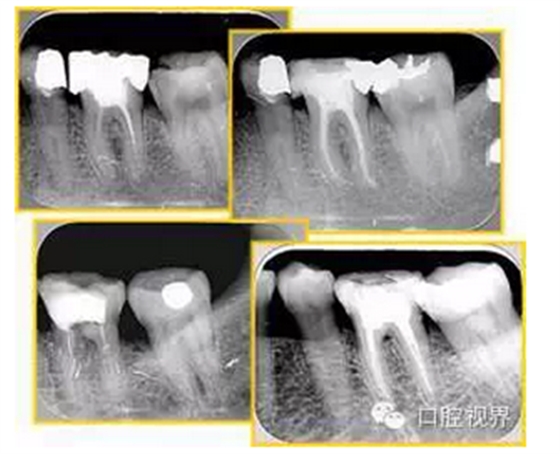

6. 鈣化

常見有修復性鈣化和增齡性鈣化。下面為根管鈣化 X 線片。

解決方法: ( 1 )清楚根管系統(tǒng)解剖形態(tài)。 ( 2 )安全頭的金剛砂鉆開髓,低速球鉆磨除鈣化牙本( ET20 ,ET40 ,DG-16 )。 ( 3 )徹底去除髓腔周壁的牙本質齡。 ( 4 )借助化學性藥劑,如EDTA 等。

( 5 )初銼選用 8# 或 10#K 銼,平衡力法探察到工作長度 , H銼上下提拉法使根管擴大,提高工作效率

7. 器械折斷

右圖及下圖為器械折斷的 X 線片。箭頭處示折斷器械。

解決方法: ( 1 )取出。 ( 2 )通過。 ( 3 )重新確定工作長度,充填。 ( 4 )根尖手術。

器械折斷可以不用取出,取出的原因多是患者心理因素。留在里面的器械關鍵是進行消毒,預防性使用抗感染藥物,預防感染。